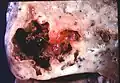

Lung abscess is a type of liquefactive necrosis of the lung tissue and formation of cavities (more than 2 cm)[1] containing necrotic debris or fluid caused by microbial infection.

Pathology image of a lung abscess. -